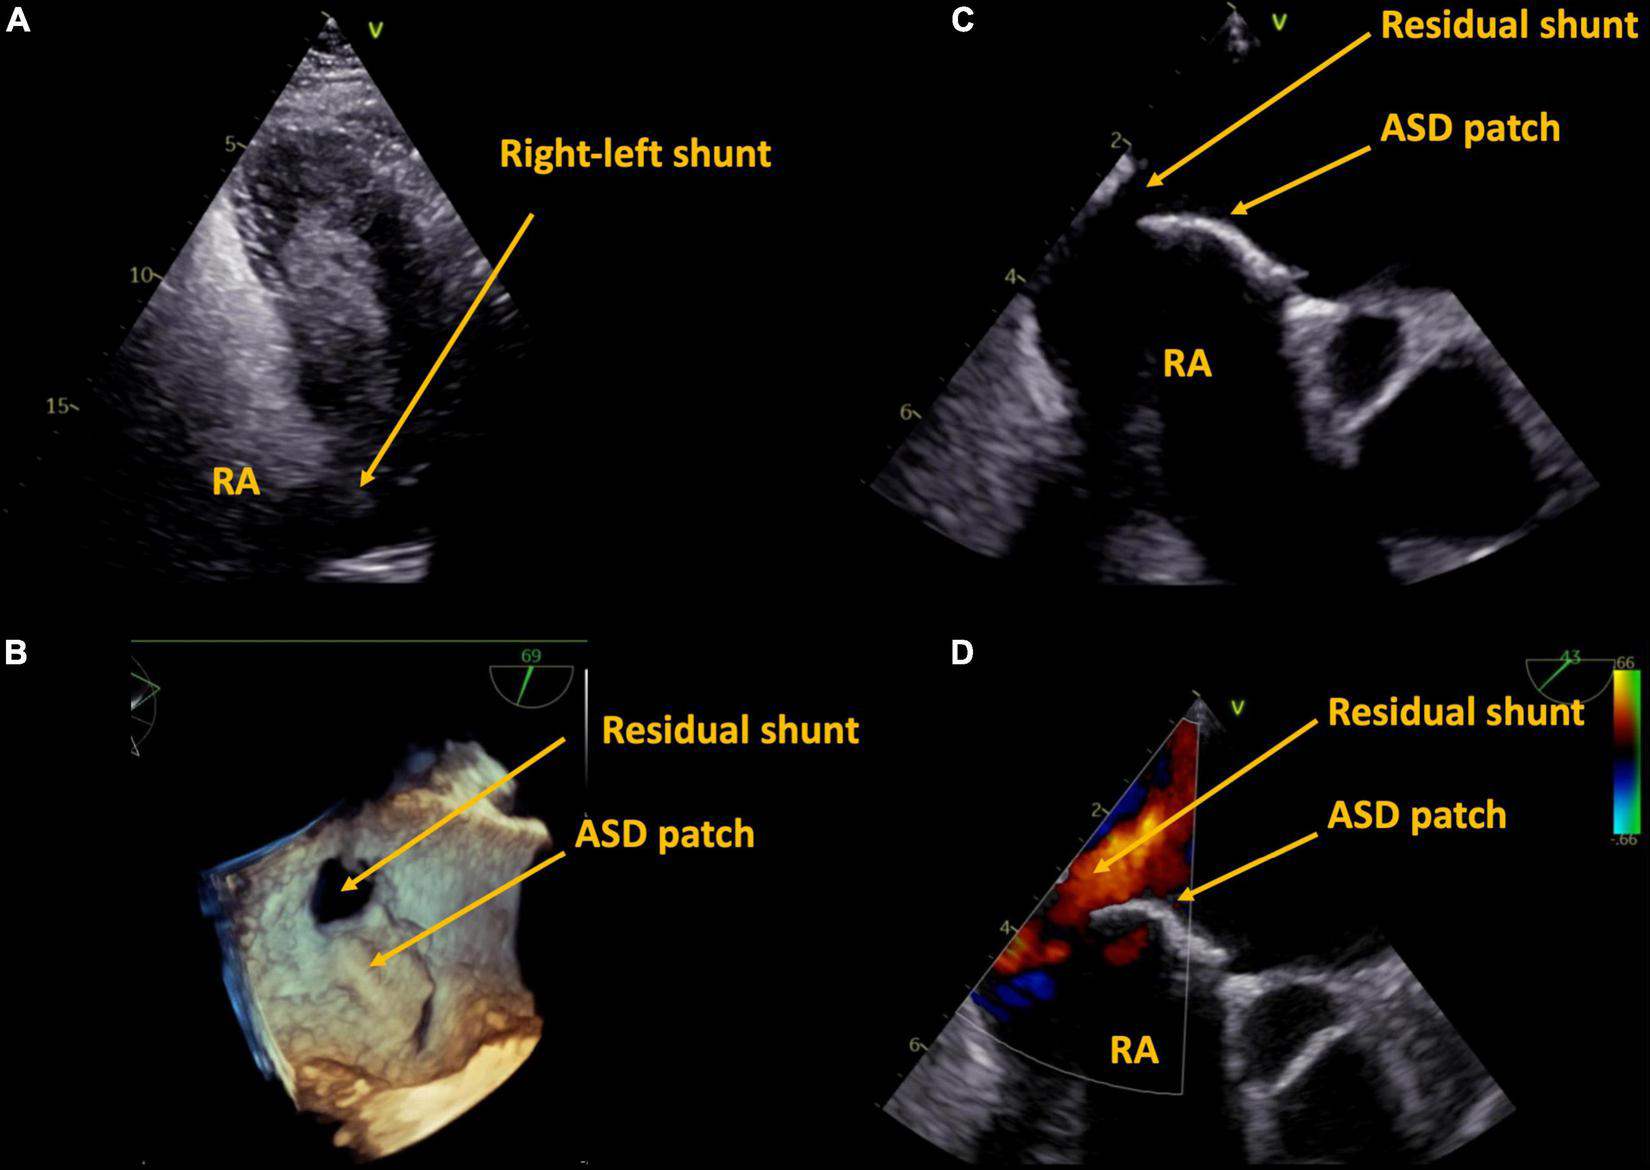

FIGURE 2

Case 1, 59 year-old patient with a history of surgical ASD closure with partial detachment of the patch. Residual shunt shown by right-heart contrast agent (A), and by transesophageal echocardiography in 3D (B), 2D (C), and 2D color (D). ASD, atrial septum defect, RA, right atrium.